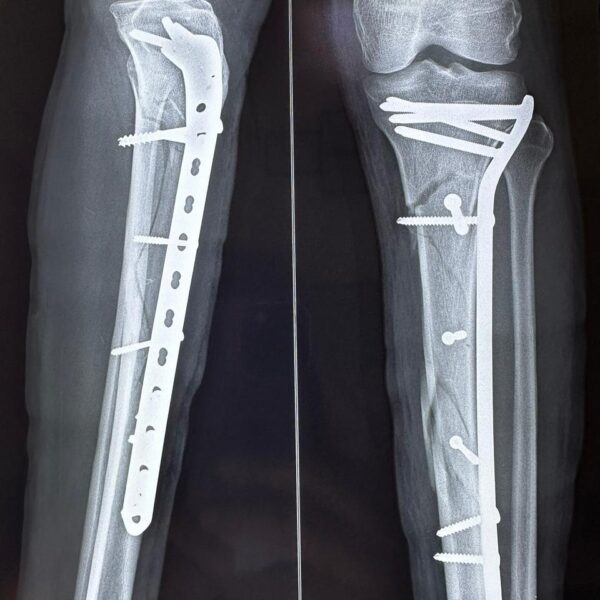

Moments That Mark Meaningful Recovery

Witness real patient transformations at The Ortho Clinic through images that reflect successful treatments and restored mobility.